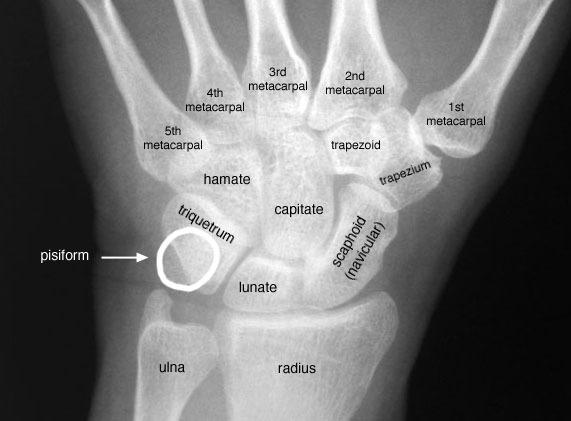

Location of carpal bones